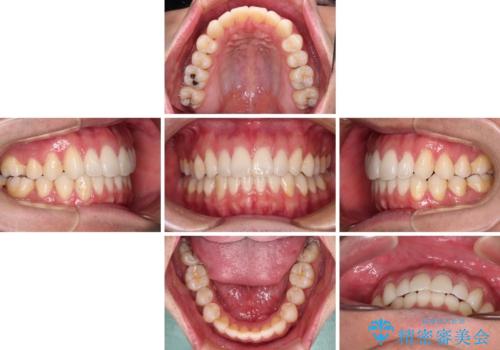

- 全体的なデコボコと、前歯の前に出ている感じを気にして来院された患者様です。

患者様と相談の上、非抜歯にてインビザラインを用いて矯正治療を行うこととし、IPR(歯と歯の間)並びに歯列全体の後方移動により口元の突出感の改善することとしました。

お仕事が忙しい方で、装着時間が不足したり、定期的な通院ができなかったりと、自己管理が重要なインビザラインによる矯正治療が長期化する要因が重なり、5年ほどの期間を要しました。